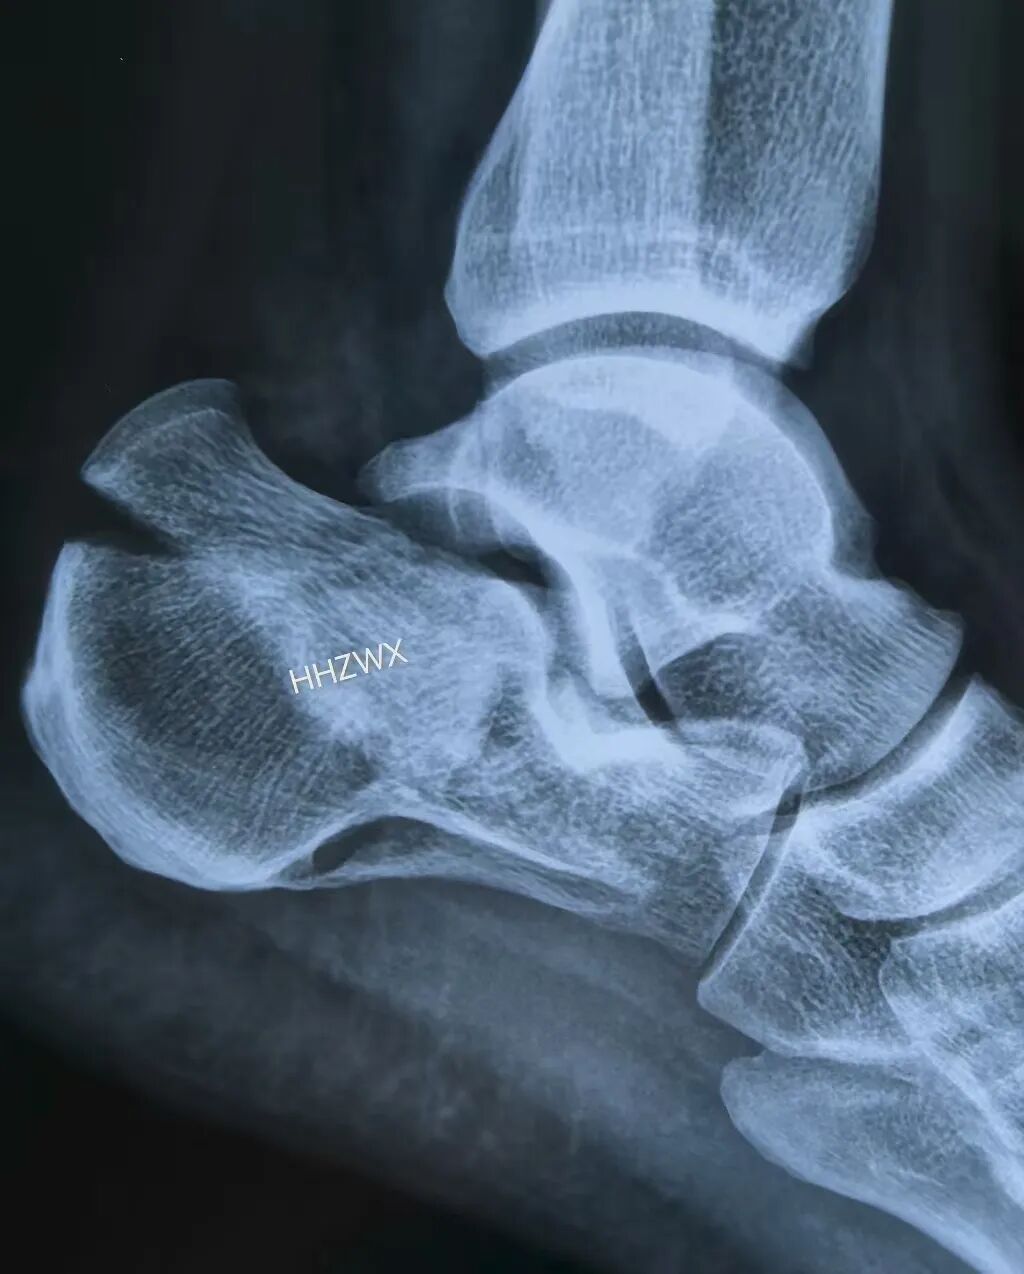

这个图提出了跟骨两个重要的角度,Gissane角和Bohler角(这两个角度其实也是跟骨骨折复位后的重要评价标准)

足正位X线片显示跟骰关节骨折(体现了足正位X线片的意义)

跟骨骨折的主要骨折线在这个示意图上展示的很好。